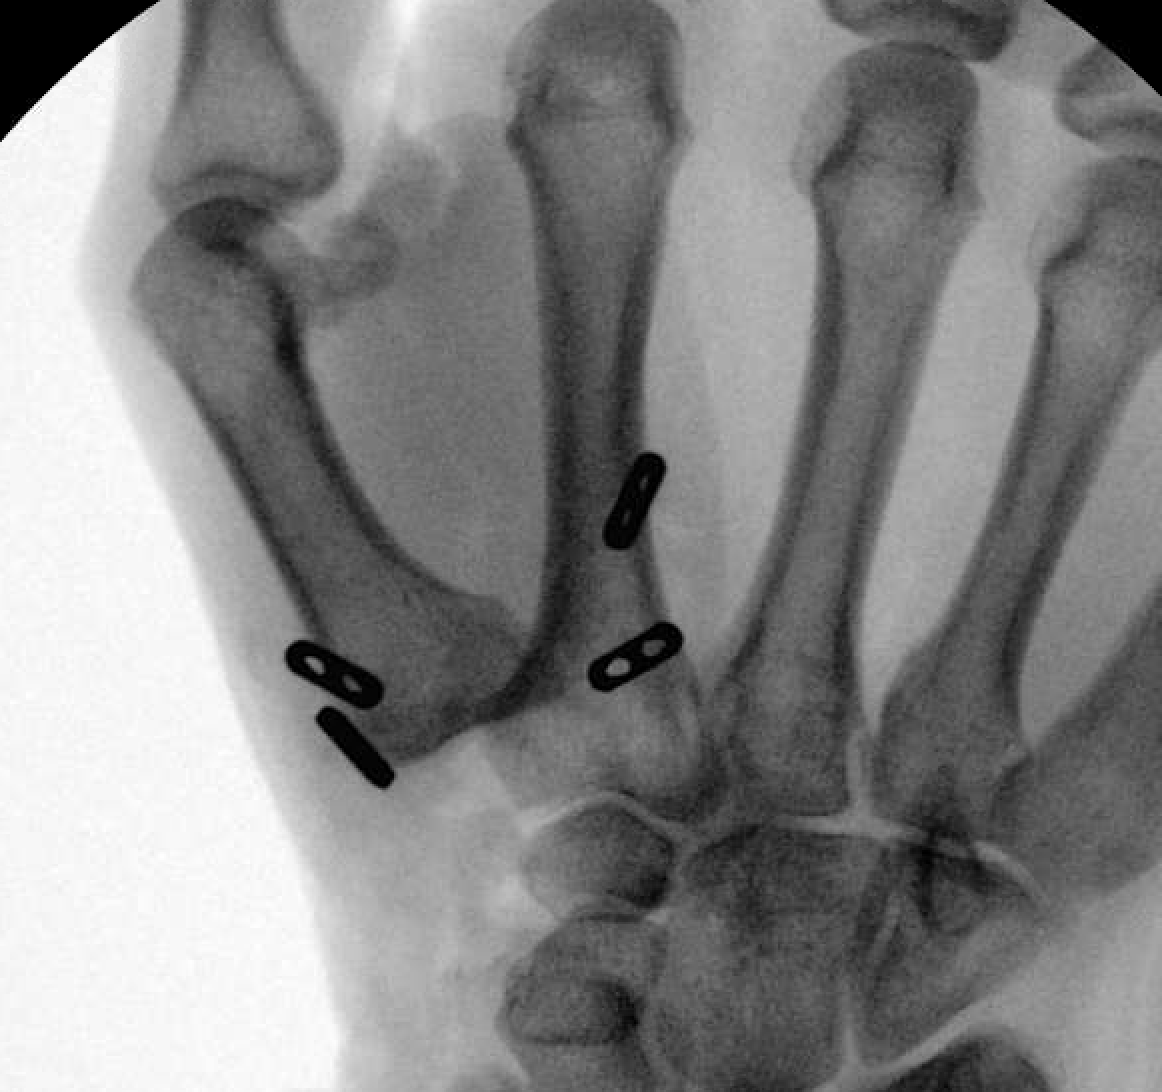

X-ray of a hand after thumb CMC arthroplasty with removal of the trapezium. In this patient, thumb metacarpal positioning is maintained by a tendon procedure (APL/FCR sling).

Reproduced from Weiss A-P, Goodman AD. Thumb Basal Joint Arthritis. J Am Acad Orthop Surg 2018;26(16):562-571.

• Placing a temporary pin or a permanent suture (stitch) from the thumb metacarpal to the index finger metacarpal to keep the thumb metacarpal in place

X-ray of a hand after thumb CMC arthroplasty with removal of the trapezium. In this patient, thumb metacarpal positioning is maintained by permanent suture with suture buttons.